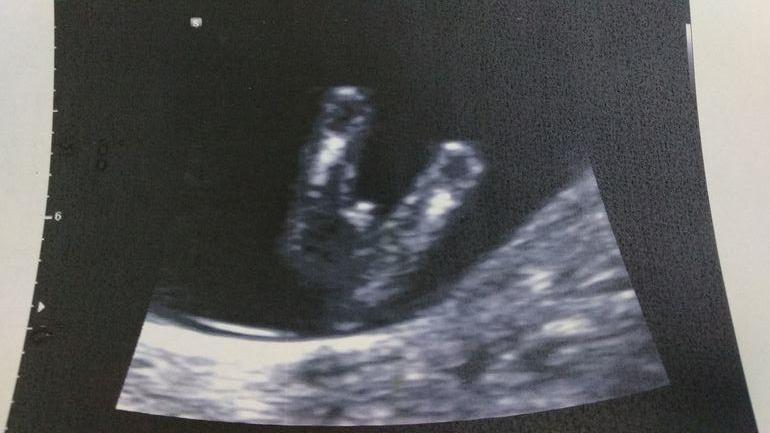

Вот фото с узи, может кто понимает, как они определяют)))) Точно скорее всего мальчик?

Лично увидеть нужно фото хозяйства. Если оно есть, то сомнений не будет. Плюс оборудование плюс врач. Мне не соврали ни в первый раз ни во второй. Но у меня мальчки прям мальчки не прячутся и фиг там спрячешь ))

Мой мальчик в 12 и 3.

Мальчик 99 и 9 судя по УЗИ вашему . Очень задран половой бугорок . У девочек так не бывает . Мне оба раза в 10 недель правильно про сказали . В этот раз ещё и нипт подтвердил потом